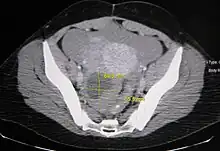

Ovarian cysts are usually diagnosed by ultrasound, CT scan, or MRI, and correlated with clinical presentation and endocrinologic tests as appropriate.

Ultrasound

Follow-up imaging in women of reproductive age for incidentally discovered simple cysts on ultrasound is not needed until 5 cm, as these are usually normal ovarian follicles. Simple cysts 5 to 7 cm in premenopausal females should be followed yearly. Simple cysts larger than 7 cm require further imaging with MRI or surgical assessment. Because they are large, they cannot be reliably assessed by ultrasound alone; it can be difficult to see posterior wall soft tissue nodularity or thickened septation due to limited ultrasound beam penetrance at this size and depth. For the corpus luteum, a dominant ovulating follicle that typically appears as a cyst with circumferentially thickened walls and crenulated inner margins, follow up is not needed if the cyst is less than 3 cm in diameter. In postmenopausal patients, any simple cyst greater than 1 cm but less than 7 cm needs yearly follow-up, while those greater than 7 cm need MRI or surgical evaluation, similar to reproductive age females.[9]